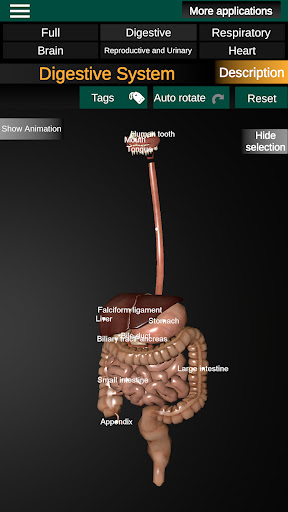

* Травна система, включаючи шлунок, тонку кишку, товсту кишку та анімацію цієї системи.